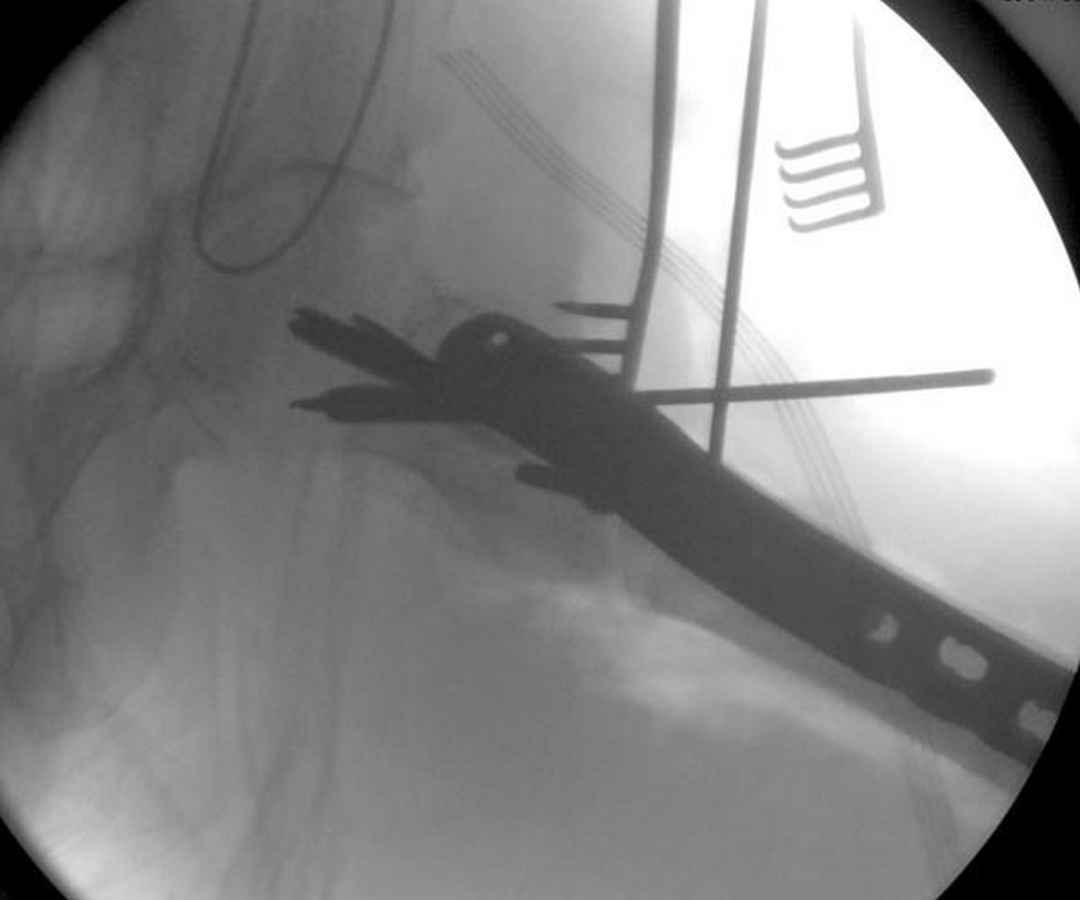

судя по картинкам с ЭОПа явно использовались приемы непрямой репозиции под его контролем, а так же интраоперационный ЭОП-контроль положения винтов, без такого контроля операция может ухудшить ситуацию (опять же учтите сроки) т.к. результат буде зависеть в большей степени от искусства хирурга, а не от технологии